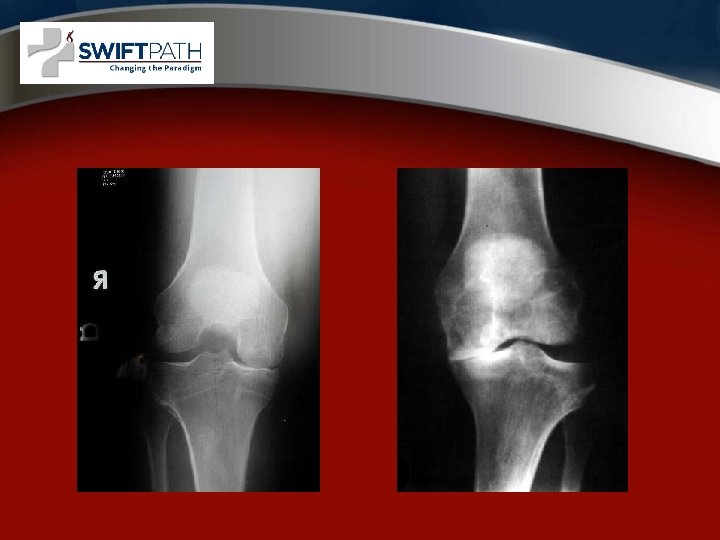

Surgical options • Arthroscopy • Partial Knee Replacement • Total Knee Replacement

COMPUTER NAVIGATION AND ROBOTIC NAVIGATION IN JOINT REPLACEMENT

Surgical Technique • General principles • Minimally Invasive Surgery “MIS”, “Miniincision” • Computer Assisted Surgery or “Navigation” • Robotic - MAKOPLASTY

MIS Knee Replacement • • Faster Recovery Improved Quads Function Less Pain Smaller Incisions Better ROM More Radiographic Outliers Computer Navigation Recommended